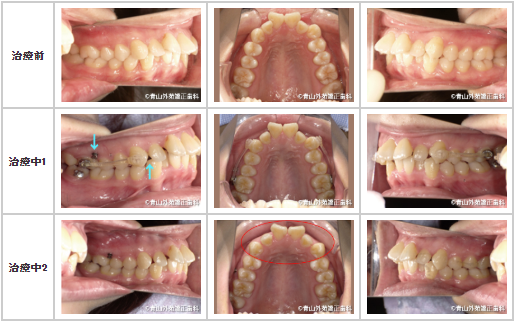

【症例3】20代女性

治療前:左側は大臼歯遠心移動装置からマウスピースに顎間ゴムをかけます。

右側は歯の動きをより確実にするため、大臼歯遠心移動装置から矯正用インプラントに顎間ゴムをかけることにしました。

治療中1:大臼歯遠心移動装置を効果的に使う事で、前歯部全体的に歯間に隙間が広がってきました。

治療中2:前歯部全体に隙間が広がってきました。